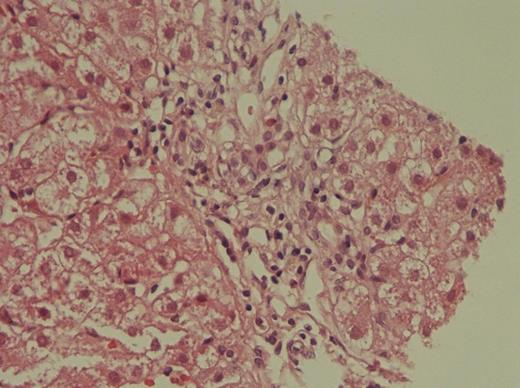

A previously healthy and normal family history 15 years old boy presented with epistaxis, pallor, jaundice, choluria and slightly hepato and splenomegaly, which were confirmed with full body CT scan, and no other alterations were detected. Remarkable results from AMA designated disease/organ panels were Hb 11.7 g/dL, adjusted reticulocytes 0.26%, neutrophils 0.931 K/µL, platelets 5.0 K/µL, ALT 1920 U/L, AST 2300 U/L, conjugated bilirubin 17 mg/dL, unconjugated bilirubin 15 md/dL, ferritin 1135 ng/mL. Supportive care was given and study for pancytopenia and hepatitis was started. Negative results from complete autoimmune panel including anti-LKM, anti-smooth muscle and anti-mitochondrial antibodies; panels for all hepatitis viruses, HIV, STORCH, EB, CMV, PVB19 and leptospira were negative. The patient was prepared for biopsies. Liver biopsy showed steatohepatitis, grade 2 fibrosis and lymphocyte infiltrates. Bone marrow biopsy showed 5% cellularity with absence of myeloid and megakaryocytes precursors, only erythroblasts and lymphoplasmocytoid cells; flow cytometry reported no abnormal cells and G-band karyotypes with and without mitomycin were normal. While the results from the biopsies the hepatic function improves but pancytopenia worsened to Hb 6.4 g/dL and neutrophils 0.124 K/µL. IHAAA was diagnosed and the patient continues with supportive care while results from siblings for allogeneic transplant arrive.